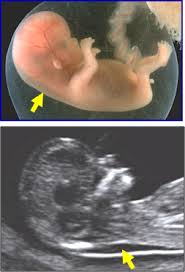

Para algunas, la primera ecografía será la de la confirmación del embarazo en las primeras semanas de gestación. Se mide el tamaño del feto, se observa la cantidad de embriones y el sitio de implantación del embrión para descartar un posible embarazo ectópico. Permite determina

r si hay uno, dos o más embriones, conocer la posición en el útero, escuchar los latidos cardíacos y medir al feto para determinar si se ajusta al tiempo real de gestación.

También se realiza la medición del pliegue nucal, el marcador ecográfico precoz más sensible y específico de sospecha de Trisomía 21 o Síndrome de Down.